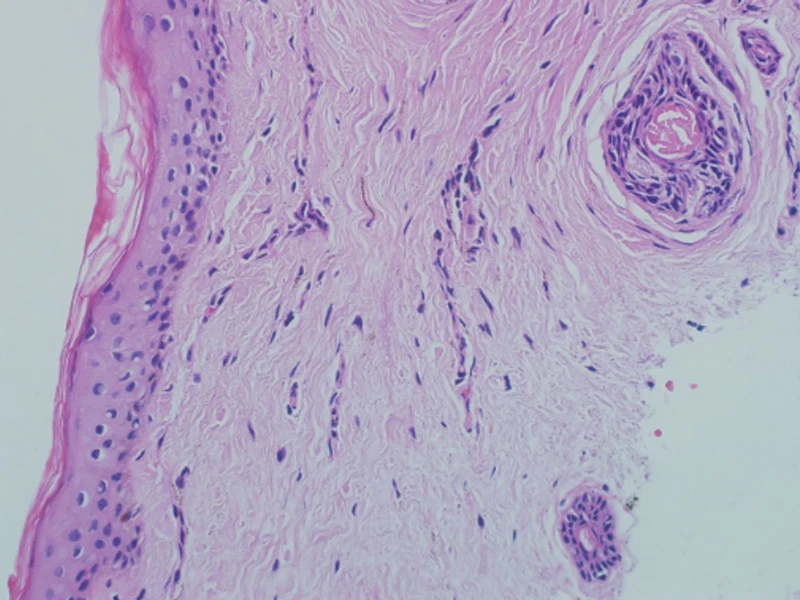

Эффективность PRX-T-терапии доказана клиническими исследованиями и многолетней клинической практикой. При окраске биоптатов кожи гематоксилин-эозином после обработки PRX-T получено доказательство, что увеличилась относительная ширина дермы, а также усилился неоангиогенез в глубоких слоях дермы, произошло нарастание отложений коллагена и нейтральных мукополисахаридов в экстрацеллюлярном матриксе дермы, заметно усилился синтез коллагена I и III типов.

Дерма до PRX-T-терапии

Дерма после PRX-T-терапии